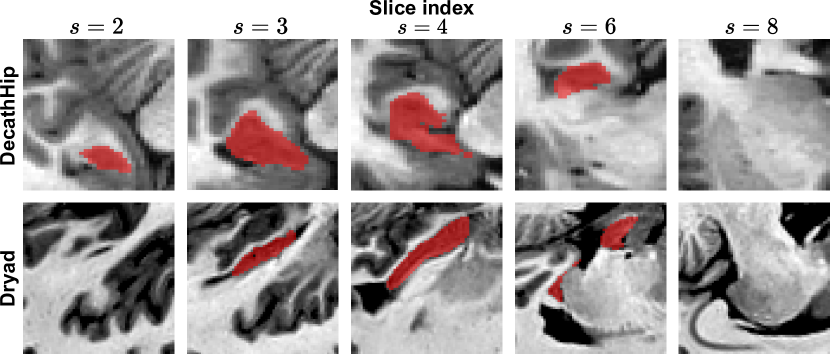

Data: Following previous work on medical continual segmentation [9, 10, 28, 27], we evaluate on the tasks of segmenting the prostate and hippocampus in, respectively, T2-weighted and T1-weighted MRIs. The hippocampus data consists of three datasets: Multi-contrast submillimetric 3 Tesla hippocampal subfield segmentation (Dryad) [19], Harmonized Hippocampal Protocol dataset (HarP[36] and the hippocampus data released for the Medical Segmentation Decathlon (DecathHip[1]. We train in the order DecathHip\rightarrowDryad following the setup in previous works [8]. We preserve HarP for OoD testing. The sets contain 260, 50, and 270 samples, respectively. The prostate data originates from five institutions using different devices and acquisition parameters [23]. We train in the order BIDMC\rightarrowI2VCB\rightarrowHK\rightarrowUCL, creating a challenging setting by starting with the smallest dataset and alternating between datasets with and without an endorectal coil. The segmentation mask encompasses the central gland and peripheral area. We likewise use the final dataset, RUNMC for OoD evaluation. Each dataset contains 12 to 30 samples and is randomly divided into 20%percent2020\% testing, 56%percent5656\% training, and 24%percent2424\% validation. A qualitative comparison of the data used can be found in Fig. 2. We also utilize synthetic OoD data. Here, we augment the test sets with common MRI artifacts (random bias field, spiking, or ghosting) doubling their size. A few examples of augmented MRIs are depicted in Fig. 3.

Figure 3: Augmentations applied to the hippocampus (top row) and prostate (bottom row) datasets to create challenging OoD scenarios.